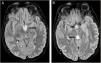

Wernicke’s encephalopathy